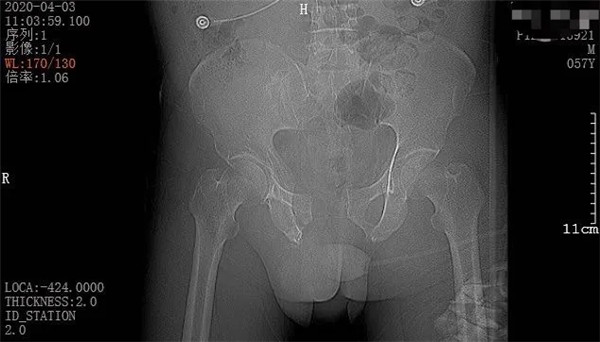

4月3日一早,和往常一樣,家住六橫的趙大叔騎著三輪車去買菜,誰知經(jīng)過下坡路時剎車失靈,趙大叔重重地撞上了一根柱子后,三輪車壓倒了他身上。趙大叔頓時感覺身體疼痛不已,無法轉(zhuǎn)身、站立。在路過市民的幫助下,他迅速被送至當?shù)蒯t(yī)院。經(jīng)CT拍攝顯示,趙大叔骨盆骨折、腹腔積血。此時,大叔突然出現(xiàn)了呼吸急促、血壓不穩(wěn)定等情況,聞訊而來的家屬當即表示要到廣安醫(yī)院治療,并火速聯(lián)系車子送往我院。

CT檢查報告